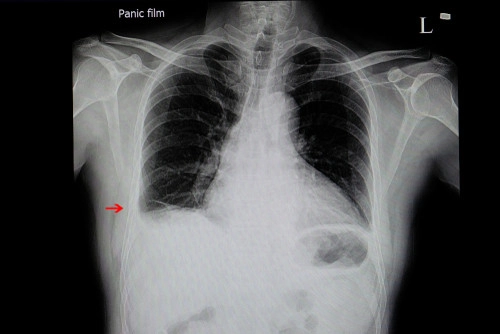

L’hémothorax est suspecté cliniquement et confirmé par imagerie :

Radiographie thoracique : révèle l’opacité liée à la présence de sang